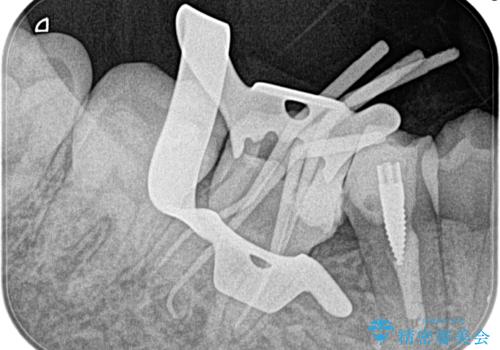

【歯根端切除術】根っこの先端の病気が治らない

- 昔他院で根管治療を行った歯の病気が再発したことを主訴に来院されました。

レントゲンにて根尖に病変を認め、根尖性歯周炎の診断のもと以下の治療をご提案しました。

1、再根管治療を行い、3ヶ月以上経過を待ち、治癒しなければ外科的歯内療法を行う。

2、外科的歯内療法を行う。

以前の根管治療の質が不明なこと、補綴処置のやりかえにメリットがあることから、1の選択肢をお勧めしましたが、費用対効果の面を患者様と相談し今回は外科的歯内療法で治療することとしました。

外科的歯内療法は根尖性歯周炎の治療における選択肢の一つです。

手術が必要ですが、通常の根管治療では解決できない解剖学的要因も解決できる可能性があります。